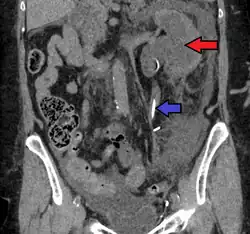

Peripelvic renal cysts may look like hydronephrosis on non-contrast CT (left image). However, CT urography (at right) reveals non-dilated calyces and pelvises.